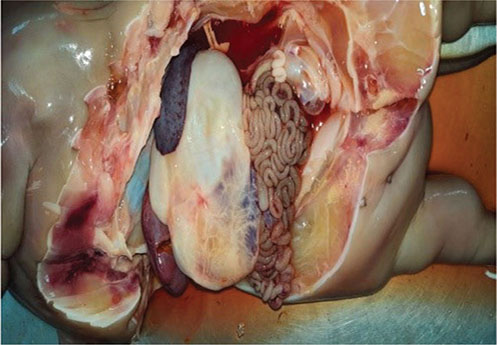

Figure 3.

Figure 3. Manually extracted dead female fetus exhibiting kyphosis and abdominoschisis

Hydroallantois was the presumptive diagnosis in both cases, based on consistent clinical presentations and diagnostic findings. Our goal was to preserve dams’ survival. Parturition was induced with 32 mg of intramuscular dexamethasone sodium phosphate (Dexona®; Zenex Animal Health, Ahmedabad, India) and 25 mg of intramuscular dinoprost tromethamine (Lutalyse®; Zoetis, Mumbai, India). In both cases, cervical dilation commenced within 5-6 hours; allantois was punctured to gradually drain allantoic fluid with a 16 French foley catheter. Initially ~ 60-80 liters of fluid was drained. To prevent hypovolemic shock, buffaloes received intravenous fluid therapy consisting of 5 liters each of Ringer’s lactate and normal saline. Supportive medication included 5 grams intramuscular streptopenicillin (Dicrysticin®; Zenex AH) and fluid therapy. Second stage of parturition (visible abdominal and uterine contractions) was observed (during fluid therapy) after ~ 15 and 17 hours of induction in Cases 1 and 2, respectively. Allanotoic fluid was collected for electrolytes estimation (Table). In Case 1, ~ 120 liters of allantoic fluid was expelled during an interval of 12-15 hours. A dead female fetus, exhibiting kyphosis at the second last thoracic vertebra and abdominoschisis with externalized viscera (Figure 3), was extracted manually. Fetal membranes were manually removed after 42 hours of induction of parturition with gentle teasing and avoiding uterine hemorrhage; had numerous small-sized cotyledons and hypoplasia. In Case 2, ~ 100 liters of allantoic fluid were drained in a controlled manner. A dead, malformed female fetus identified as chondrodysplastic dwarf (Figure 4) was removed manually; fetus had short limbs, broad thorax, flat face with mandibular prognathism, bulging eyes, and fluid-filled abdomen (Figure 5).